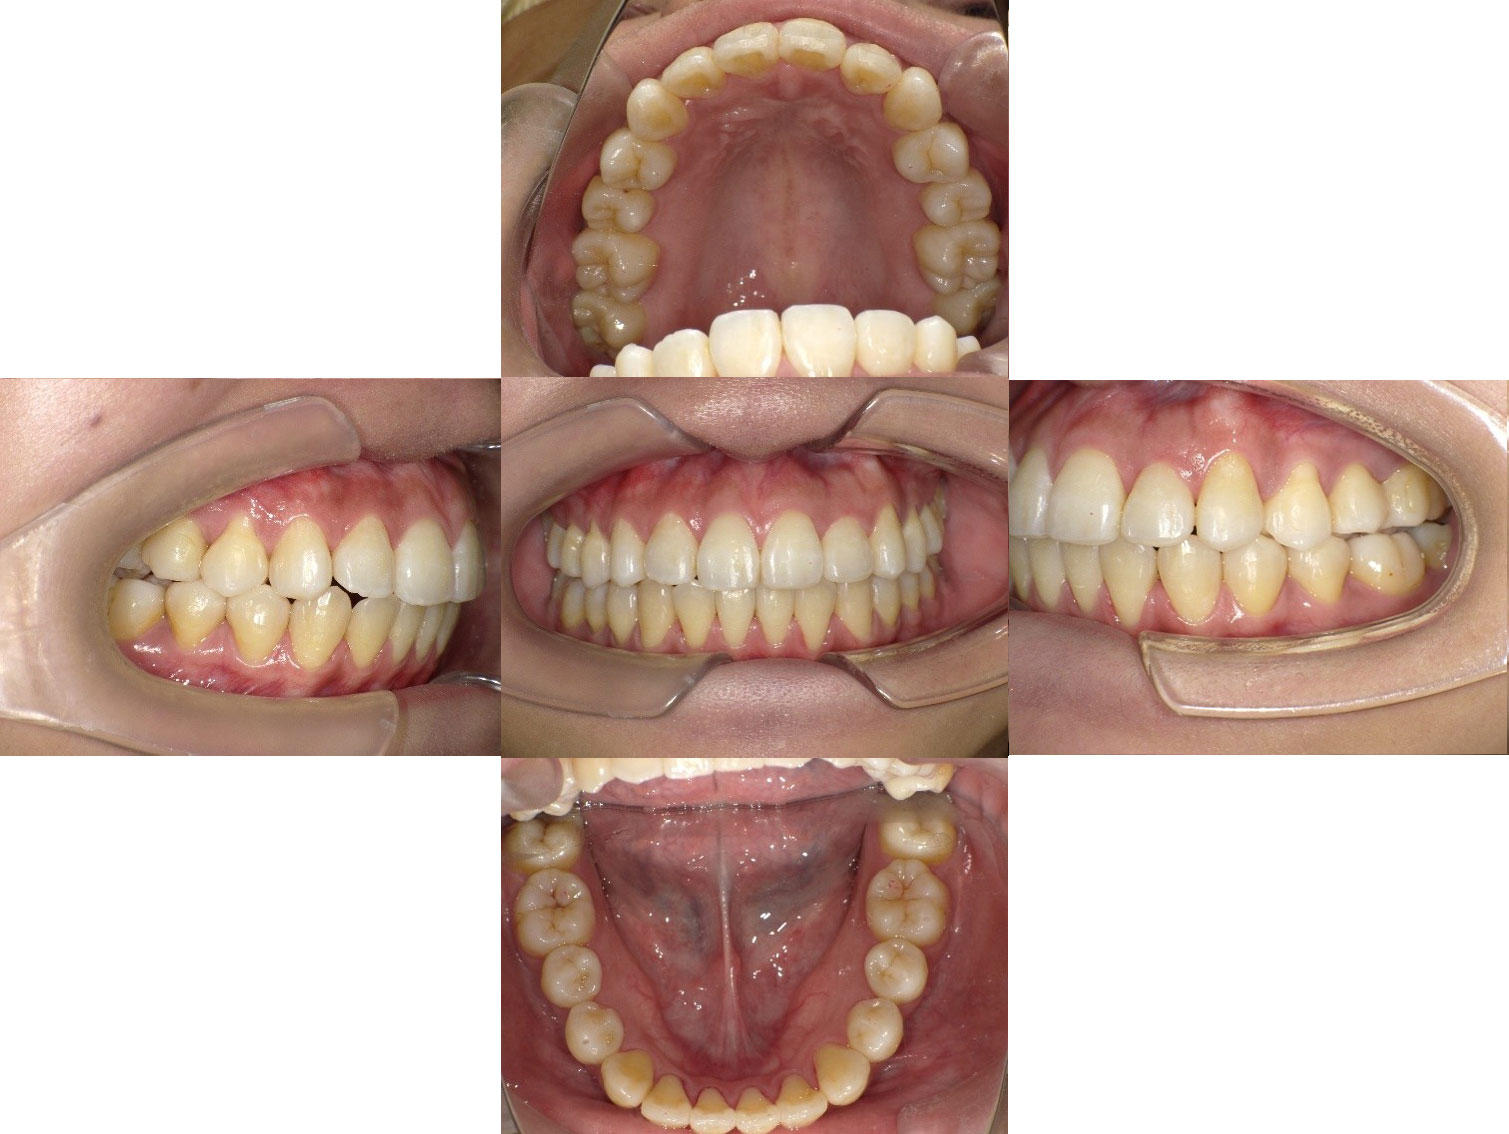

After

治療内容 ・ワイヤーによる全顎矯正

・小臼歯非抜歯

・口腔外科を紹介させていたいて上下左右の親知らずは事前に抜歯

治療期間 52か月(4年4か月)

治療回数 44回

治療のポイント 小臼歯非抜歯

この患者様も、検査の結果、小臼歯を抜歯する必要はないという診断のもと、矯正治療を行い、良好な結果を得ることができました。

ただし、親知らずは矯正治療の妨げになるという判断から、矯正前に4本抜歯しています。

当院の治療方針において、いずれの歯も抜歯することなく並べることができています。

総合的に見たらまずまず良好な結果と考えています。

患者様のご協力(ちゃんと通院してくれる・自分でかけるゴムなどをしっかりやっていただいた)もあってのことですがスムーズに進んだ結果だと考えています。

また小臼歯抜歯を行った場合よりも期間はおそらく短く済んでいると思われます。